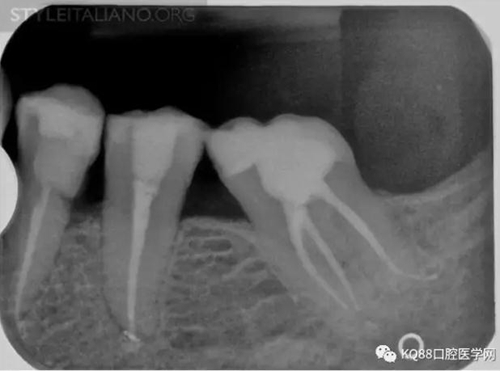

Case 3: This patient was referred for assessment of a first mandibular molar, after an attempted endodontic treatment. Mesio-lingual, mesio-buccal and one distal canal were scouted and filed and a calcium hydroxide temporary dressing was used before referral, but pain persisted. Eventually, most of the temporary obturation material was lost at the time of the visit.

Img. 6 - A careful examination of the pulp chamber floor showed the presence of a middle mesial canal in the mesial root

Img. 7 - And two canals in the distal root

Img. 8 - Endodontic treatment was completed and pain subsided.